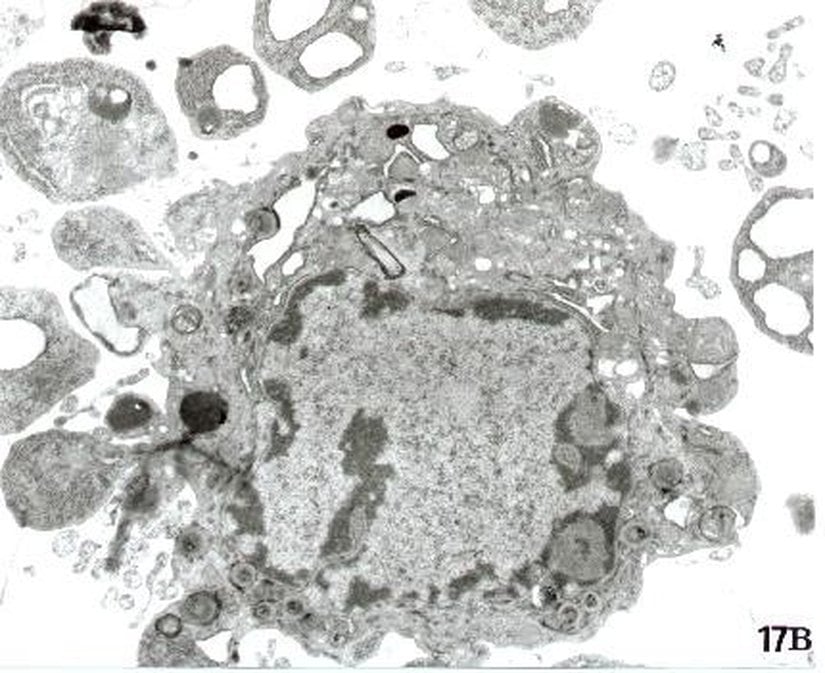

:sharpen(0.5,0.5,true)/evrimagaci.org%2Fdosyalar%2Ficerikler%2F22928298_mal17bjpg.jpg)

Bu yenilenme, ilk etapta "onarım" gibi düşünülebilir. Yani tıpkı günümüzde olduğu gibi, ilkin zamanlarda da hücreler hasarlarını onarabiliyor olmalıdırlar (hepsi olmasa da, bir kısmının yapısının buna elverişli olduğu düşünülebilir). Yani etraftaki kimyasalların kullanılarak, var olan yapının tazelenmesi... Ancak bu tazelenmenin (onarımın) hızı, hücre içerisindeki hasara yetişememeye başladığı anda, artık onarım yeterli kalamayacaktır. Bunun da basit bir sebebi vardır: Zaman aktıkça, aynı şiddetteki fiziksel kuvvetlerin etkisi dahi yapıyı giderek daha fazla aşındırmaya başlayacaktır. Ancak kimyasal onarımın hızı, yıkımı yakalayamadığı anda, mekanik hata oluşacak ve yapı dağılacaktır. Bu sebeple "sıfırlanma" veya "yenilenme" şarttır.